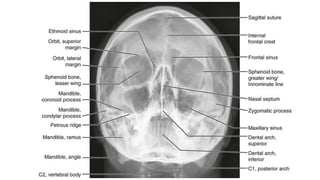

Occipitofrontal view

 This projection is used to demonstrate the frontal and

ethmoidal sinuses.

 It is also known as the Caldwell’s view.

 The patient is seated upright in front of the receptor and their

forehead and nose are placed against it.

 The beam is centred at around 15 to exit at the nasion.

⁰

• collimation

• lateral to the skin margins

• superior and inferior to the borders of the sinus cavities

z Occipitofrontal view  Thisprojection is used to demonstrate the frontal and ethmoidal sinuses.  It is also known as the Caldwell’s view.  The patient is seated upright in front of the receptor and their forehead and nose are placed against it.  The beam is centred at around 15 to exit at the nasion. ⁰ • collimation • lateral to the skin margins • superior and inferior to the borders of the sinus cavities